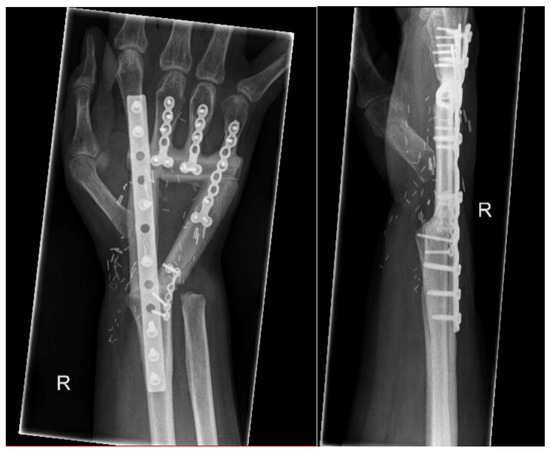

Arthrodesis of the Wrist with Vascularized Fibula Flap for the Treatment of a Large Defect of the Distal Radius

| GROUP 1 | Case 1 | Distal radius, parts of the proximal wrist | Trauma | 6 month | 32 | 9 cm | Vascularized fibula | Wrist arthrodesis | N/A N/A | 0-0-0° 40-0-50° | 60% | MMWS = 50 DASH = 24 | yes |